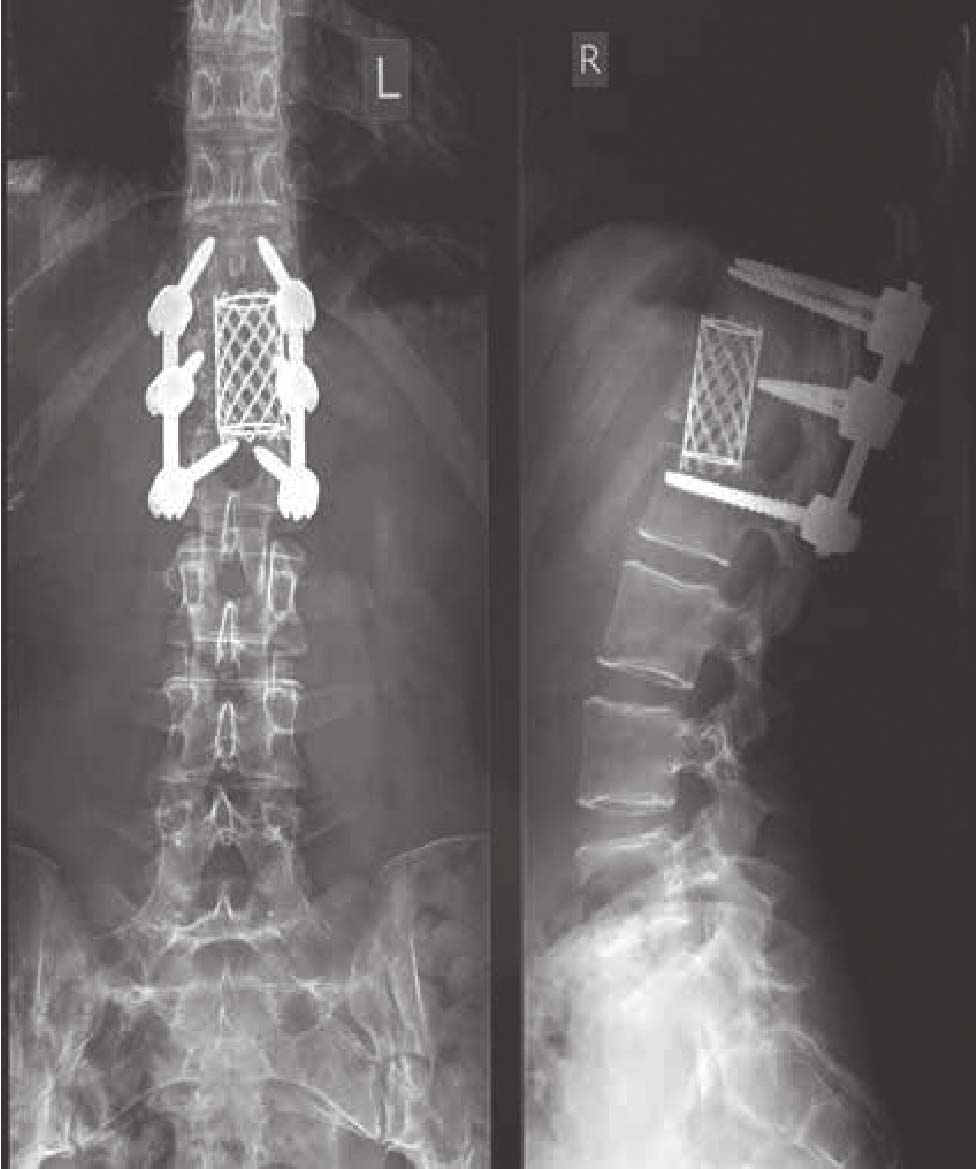

半夜,我醒过来了,独自一人在康复室。起初,我为自己还活着而感到巨大的欣慰。紧接着,巨大的疼痛席卷了全身,被钉入的钢钉像一个铁拳一样挤压着我的脊柱(见图0-1)。护士慢腾腾地走了过来,淡漠且不屑一顾。这个世界欢迎我回归的方式并不让人满意。我哭了,只想找我的妈妈。

图0-1 术后脊柱CT扫描图

我并不会触发机场安检的安全警报,但是,这些钢钉会永久地留在我的身体里。